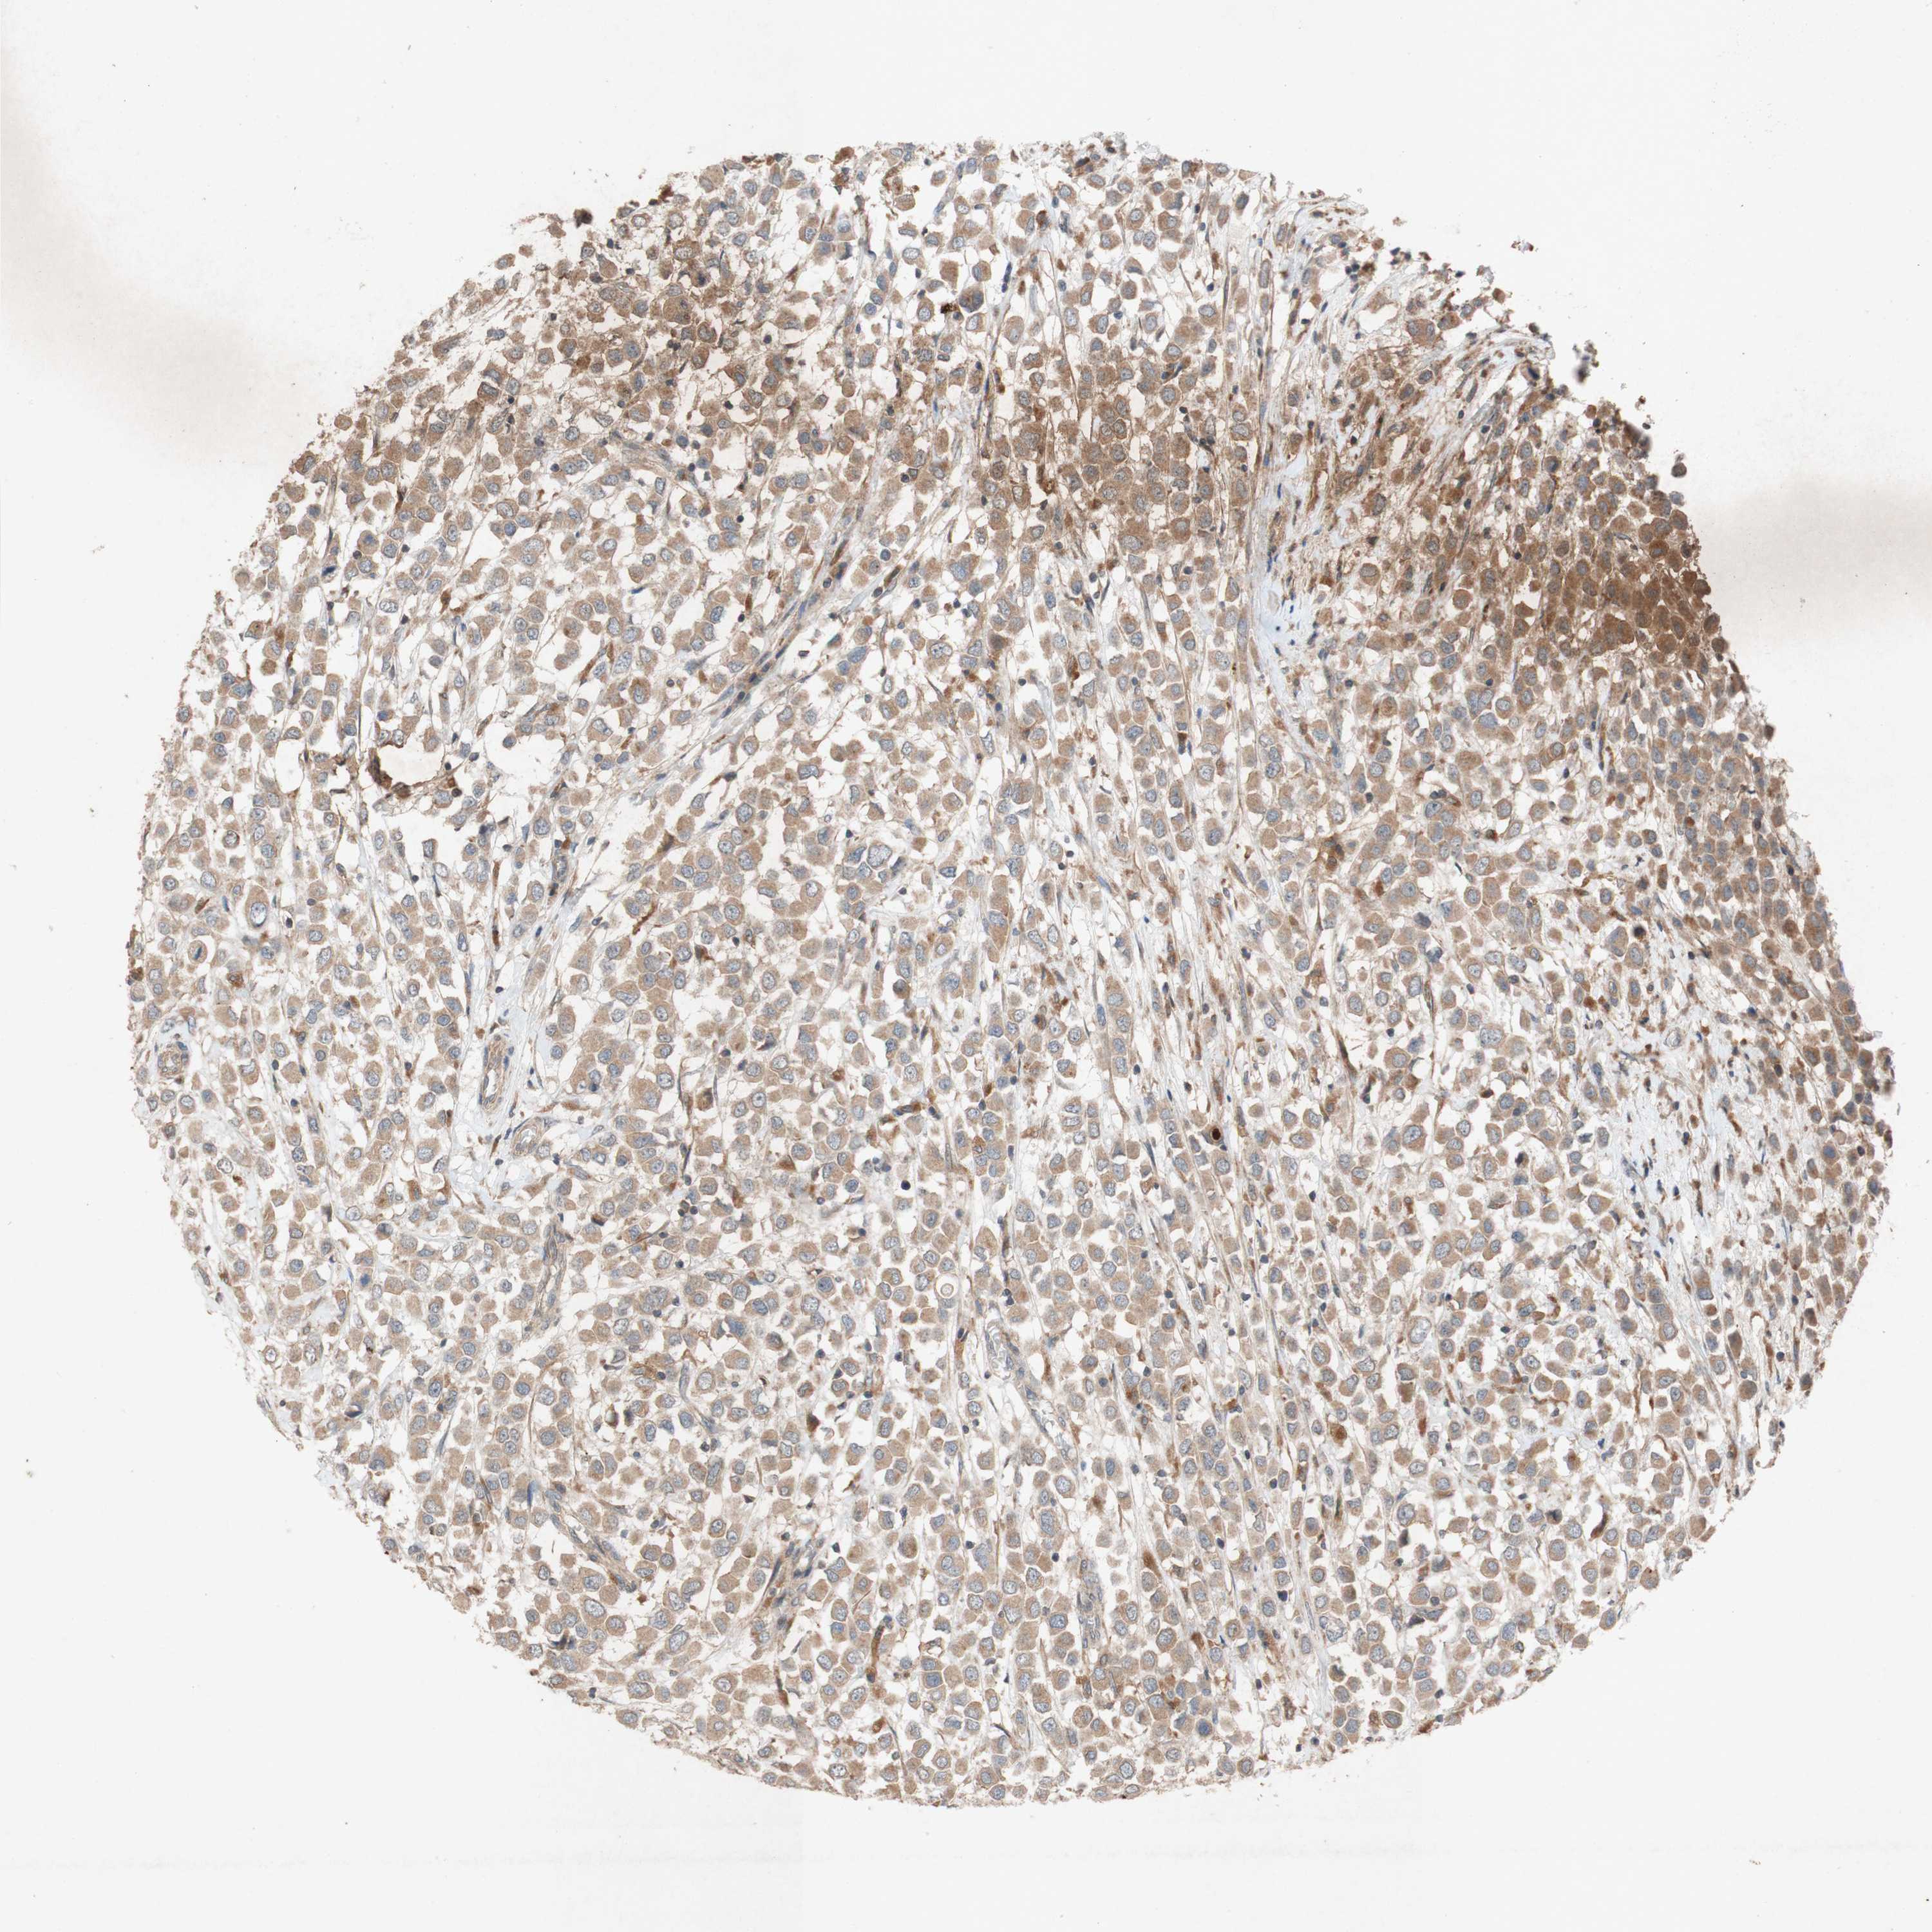

BRCA TCGA BRCA VALIDATION PROTEIN EXPRESSION